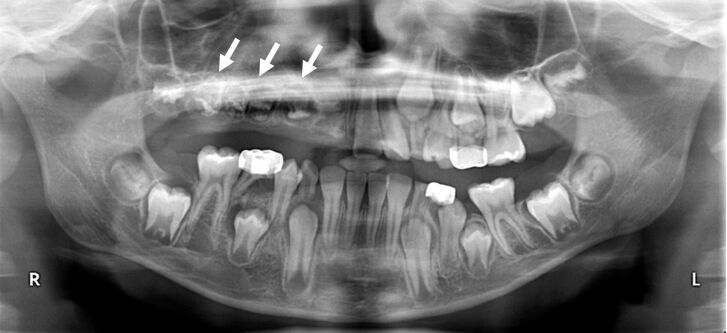

66.15歲男孩因上顎右側犬齒排列不整而來求診,經X光檢查如附圖所示,發現一放射線透過性影像如箭頭所示 之區域,相關牙齒之牙髓活性測試皆呈活性反應,在切片時發現此病變區呈現一空腔,病理鏡檢只看到少量 的纖維組織及骨小樑,並無上皮襯底(epithelial lining),此病變最可能為下列何者? (A)動脈瘤性骨囊腫(aneurysmal bone cyst) (B)中心型巨細胞肉芽腫(central giant cell granuloma) (C)局部骨疏鬆性骨髓缺陷(focal osteoporotic marrow defect) (D)單純性骨囊腫(simple bone cyst)